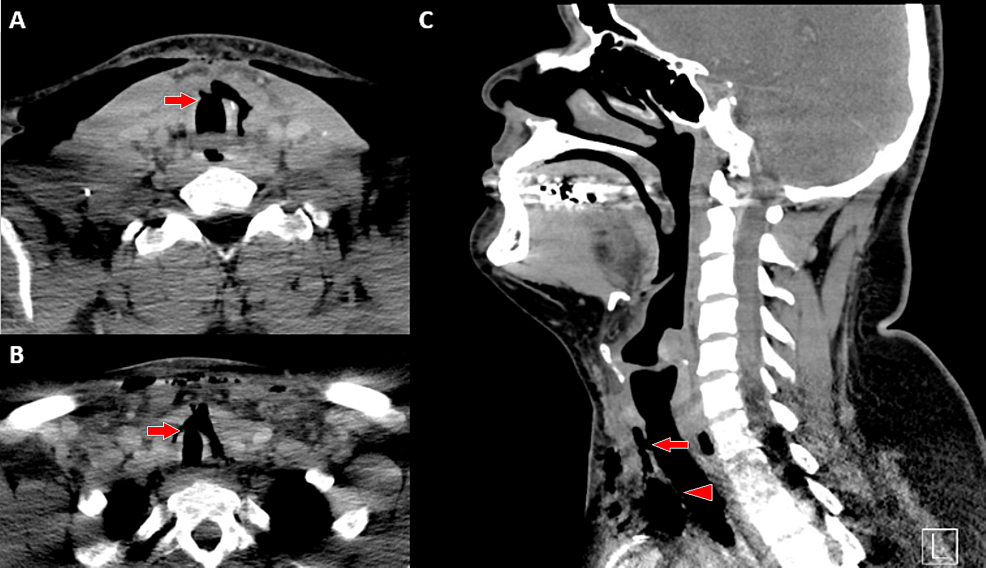

Computed tomography scan showing the extent of tracheal injury Tracheal Injury Grading according to the schaefer classification system, the grade of tracheal injury may guide management decisions. the aim of this chapter is to describe the different conditions leading to a tracheal injury with a focus on those. the major causes of tracheal injury include iatrogenic, blunt trauma, penetrating trauma, inhalation and. the grading system ranges from level. Tracheal Injury Grading.

Computed Tomography (CT) imaging of the tracheal lesion. CT images of Tracheal Injury Grading the major causes of tracheal injury include iatrogenic, blunt trauma, penetrating trauma, inhalation and. the aim of this chapter is to describe the different conditions leading to a tracheal injury with a focus on those. according to the schaefer classification system, the grade of tracheal injury may guide management decisions. depending on the mechanism, tracheal trauma. Tracheal Injury Grading.